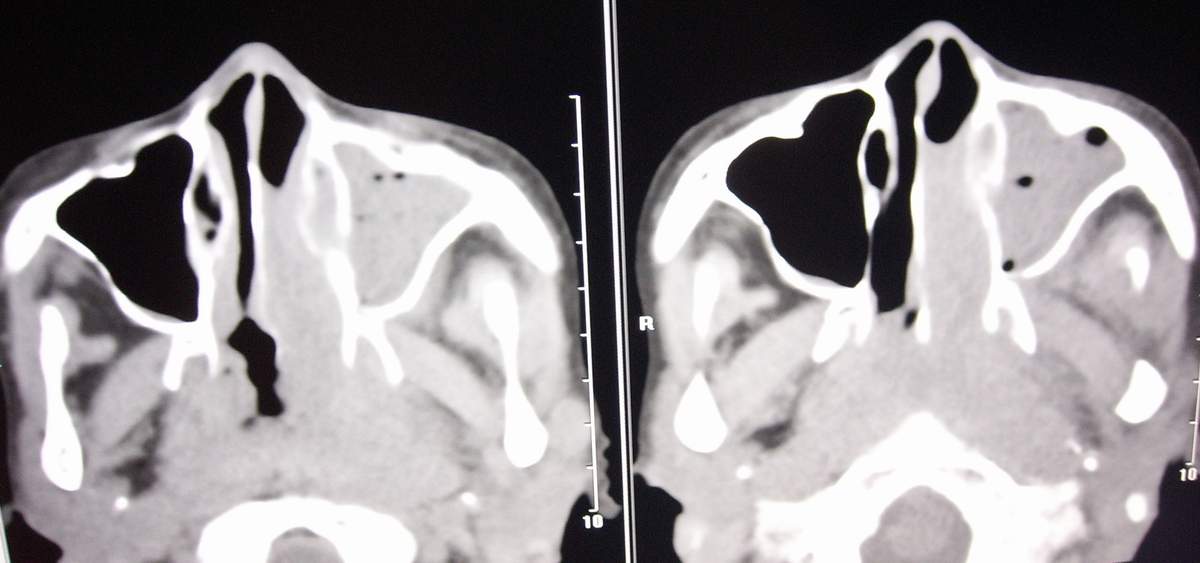

标题: CT7384:[讨论][分享]鼻咽纤维血管瘤? [打印本页]

女,57岁,病史不详。

左侧鼻腔息肉样病变,建议活检或增强扫描。左上颌窦炎。

建议增强,需除外鼻腔及鼻孔息肉伴左侧上颌窦阻塞性炎症.

图像有点少,又没有强化,不太好说。不过鼻咽部纤维血管瘤好发于年青男性

这么大年龄,首先应考虑鼻咽癌伴阻塞性鼻窦炎。

鼻咽纤维血管瘤好发于青少年,有反复鼻腔出血病史,明显强化,此病例年龄偏大,考虑鼻咽癌伴阻塞性鼻窦炎